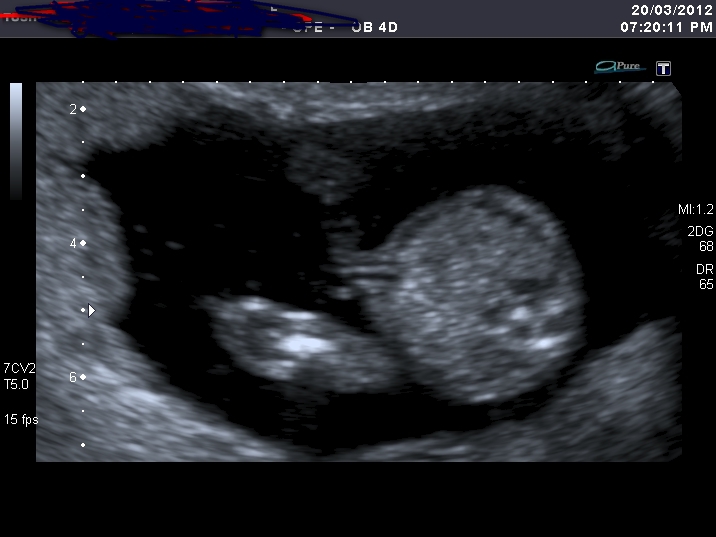

Yesterday I've had my u/s, baby looks perfectly healthy ( huge relief), but the tech was pretty sure it's a girl. I faked a happy face :worry: I'm 15weeks 5 days.

Could he be wrong? I'm hoping that SHE turns into HE by some miracle....

Any experiences with wrong u/s gender prediction, esp. girl turning up to be a boy?